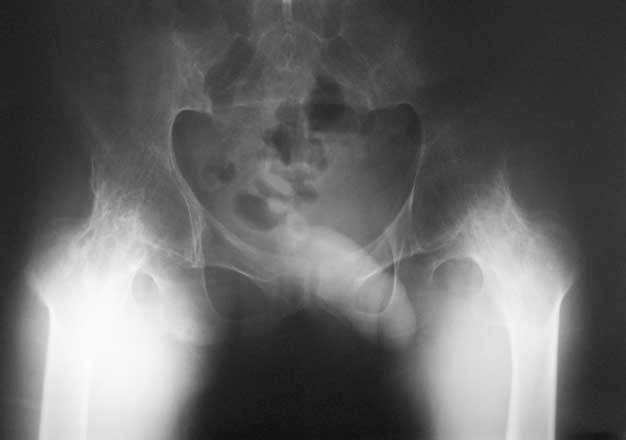

Уважаемые коллеги, в отделении находится пациент 28 лет, страдающий ревматоидным артритом с детства. В настоящее время основной проблемой для него являются тазобедренные суставы - костный анкилоз в положении сгибания около 80 град.

Привет Максим. На двух анкилозах передвигаться крайне плохо. Раз ходит - то небольшая часть мышц окружности т.б сустава есть, это видно и на фото. Пошел бы по пути разанкилозирования и бесцементник с каждой стороны поочередно.

Максим, мы протезировали 2х подобных больных. В случае с семилетним анкилозом на фоне болезни Бехтерева функция сустава осталась значительно ограниченой, но больная вполне сносно передвигалась. В другом случае на фоне ревматоидного артрита 4х летний анкизоз у молодого парня получен очень хороший функциональный результат. В обоих случаях использовали бесцементные протезы.

Следует учесть тот факт, что нечто принимаемое за хорошую кость во впадине по рентгенограмме, может оказаться очень неприятной пустотой с порозными балочками. При выборе размеров чашки это следует учесть, а в целом результаты не разочаровывают.